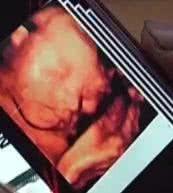

黃琴琴順利產下一名女嬰

家人為孩子取名為小葡萄

小葡萄剛出生時只有2斤半,由于在母體中僅呆了30周,她的肺部功能并沒有發育成熟。

由于母親全身燒傷面積太大,小葡萄在宮內時感染了炎癥。孩子剛出生時的情況并不是很樂觀。